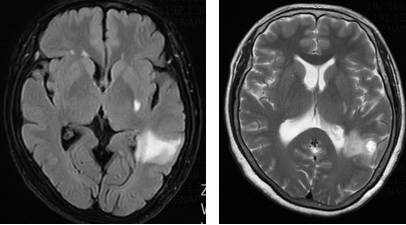

胸部CT(2023年11月10日):左肺下叶纵隔旁团块状病灶,径约21mm*30 mm。

图片1.png

胸部CT基线(2023年11月10日)